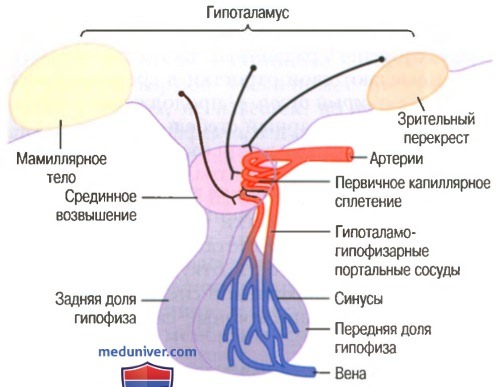

Как работает центр насыщения в гипоталамусе: визуальные иллюстрации